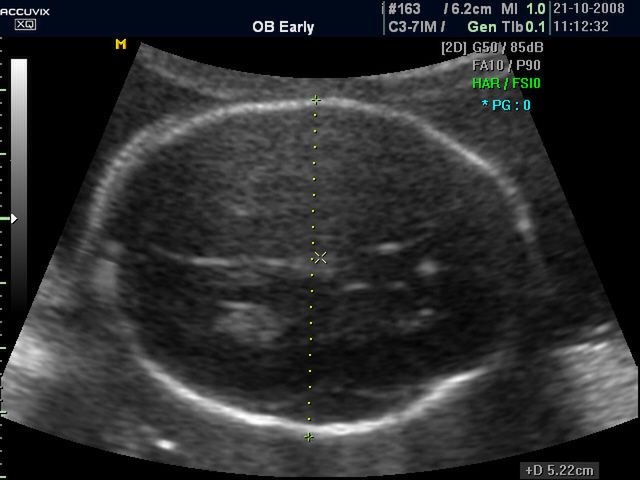

/ 10Zdjęcia płodu - główka dziecka w 25 tygodniu ciąży

Płód w 25 tygodniu ciąży, na zdjęciu widoczna głowa dziecka